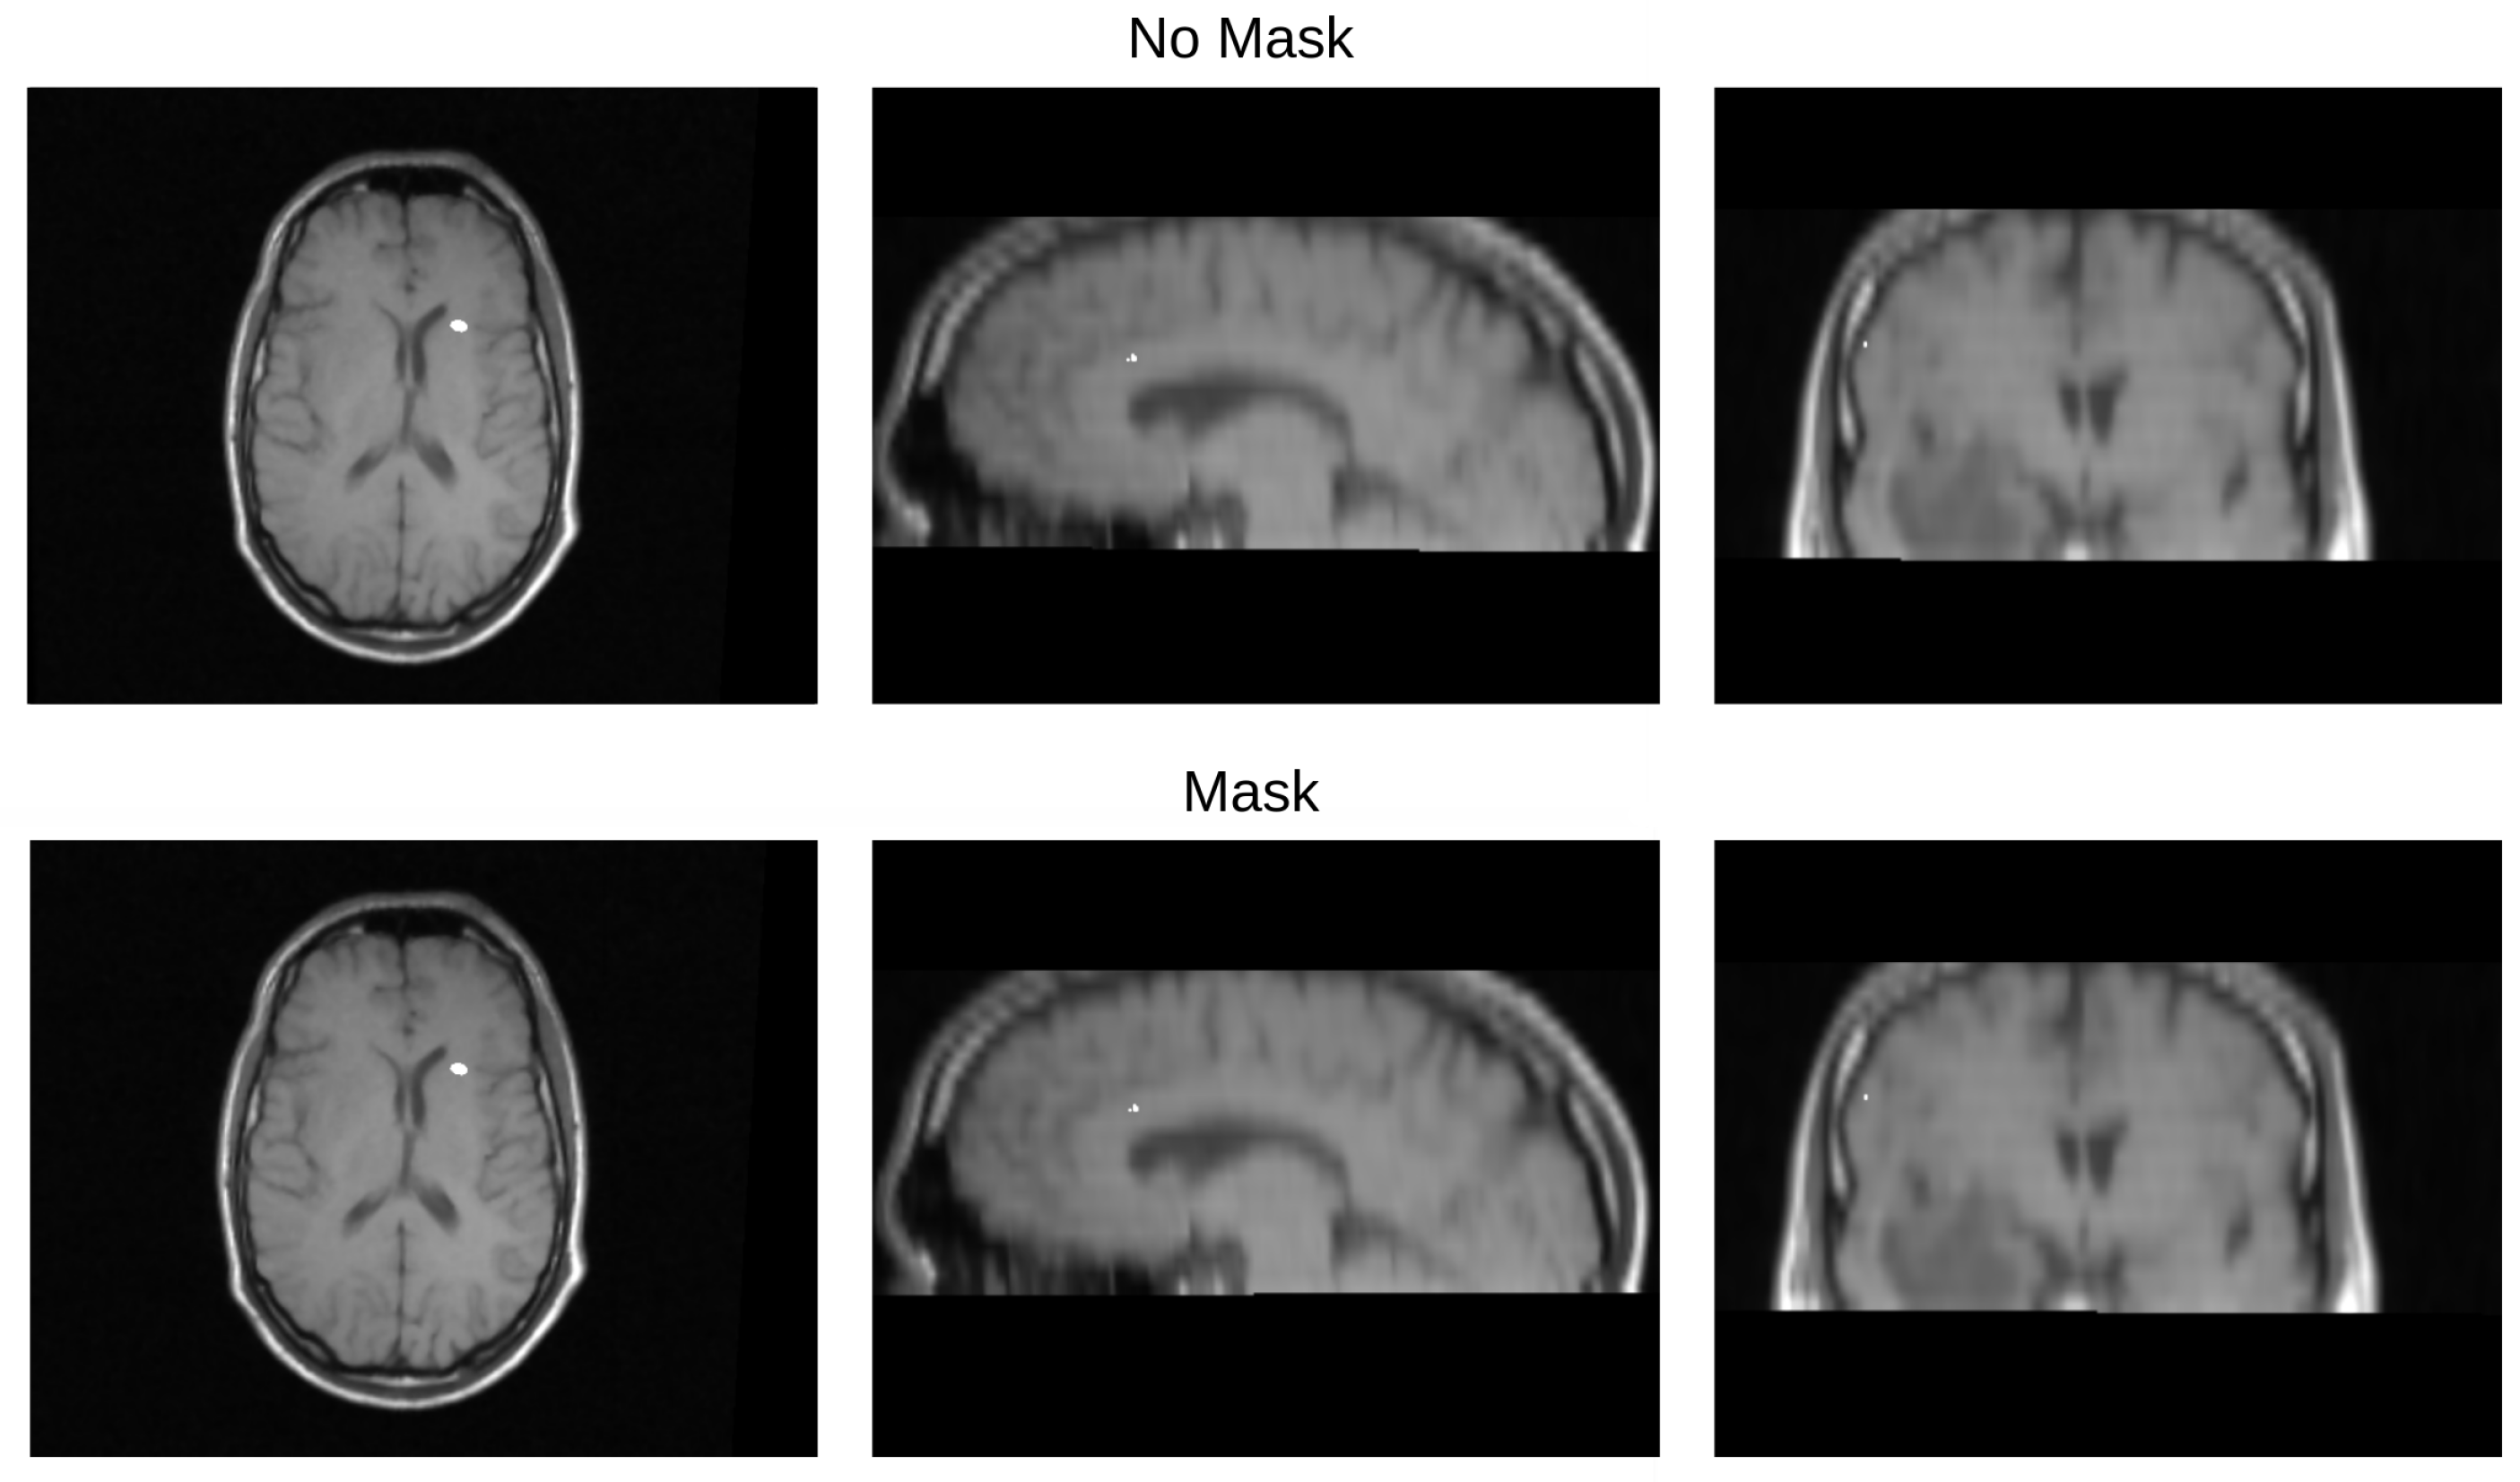

We validated the performance of the fusion method following the two methodologies in Section 3. We used eight pairs of CT and MRI from the RIRE dataset for the first method. The CT images were generated with the method described in Section 3.1.1. We compared the procedure shown in Figure 8 against a fusion procedure that does not employ a sampling mask of the brain tissue, which is shown in Figure 9. Both methods used a rigid registration with MI as the similarity metric and gradient descent for the optimization. We used descriptive statistical metrics of central tendency and variation to compare the methods using the validation from Section 3.1. These results were summarized in the box plot shown in Figure 10. For the second validation, we faced a limitation in the number of images available for evaluation. Given this constraint, we opted to compare the methods individually for each of the four cases. A scatter plot was chosen as the most suitable representation to visualize the error dispersion for both methods. Scatter plots are particularly effective in such scenarios as they allow for clear visualization of individual data points, making it easier to discern patterns or anomalies, especially when dealing with a smaller dataset. This approach provides a more transparent and detailed view of the distribution of errors across the limited set of images. The results of this comparison are illustrated in Figure 11.

Table 3 displays the Euclidean distance between the reference points and the resulting points of the transformation from the compared methods. From the data, we can observe that the difference in the Euclidean distance for our method is significantly lower in images 3, 6, and 8. This is mainly caused by the differences in the original images that have some variations in brain tissue, as shown in Figure 12, Figure 13 and Figure 14. Due to some electrodes passing through these areas with variations, the sampling in the registration does not use these voxels to compute the transformation, thus improving the registration when the mask is used. The results are represented in Figure 10, where our method using a sampling mask yields a Euclidean distance of 1.3176 mm with a standard deviation of 0.8643. In contrast, the method without a sampling mask yields a Euclidean distance of 1.2789 mm with a standard deviation of 5.2511. These findings suggest that the use of the mask improves the registration when there is a great difference in the tissue between the MRI and CT images due to the reduction in voxel sampling of these varying tissues in the registration process.

Figure 13. Image 6 fusion with no mask and with a mask.

Diagnostics 13 03420 g013